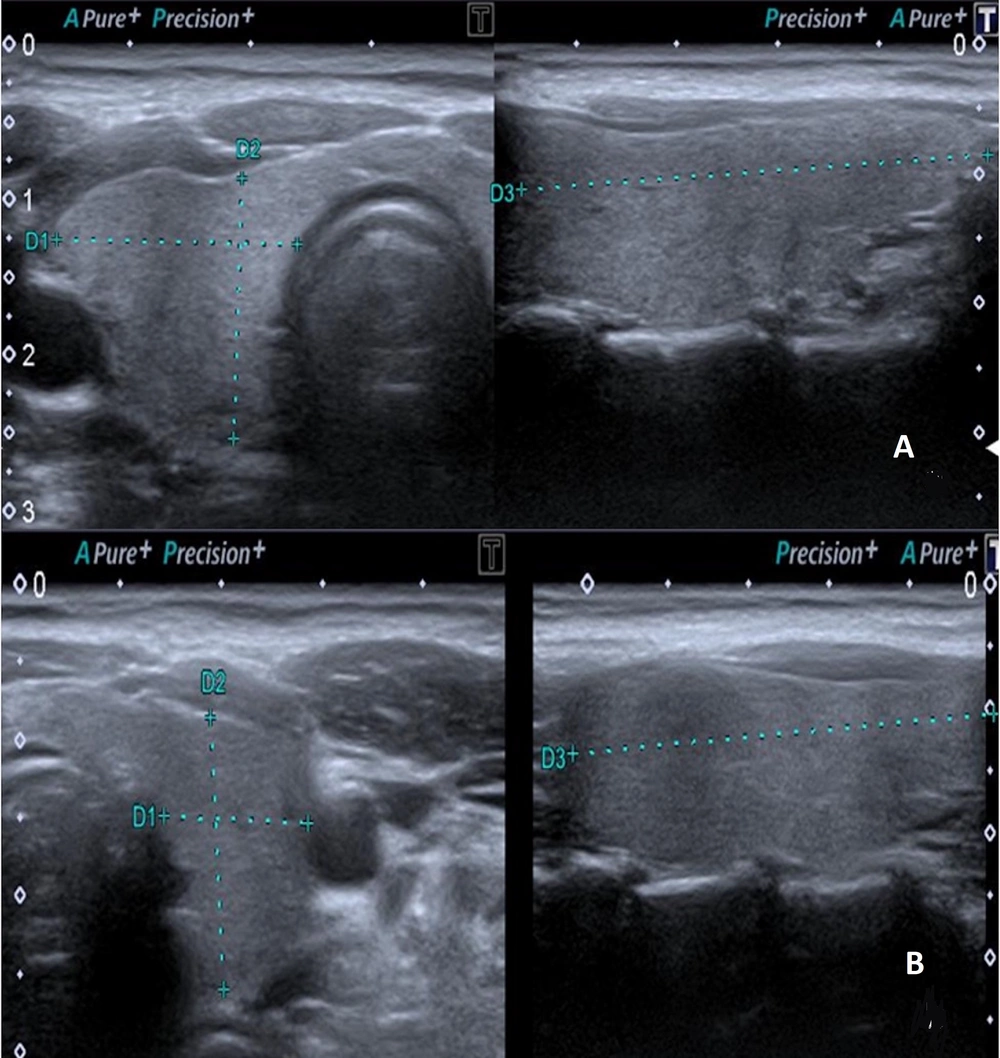

Ultrasonographic evaluation of the thyroid gland was conducted using a Canon Aplio 500 device (Canon Medical System Corporation, Tokyo, Japan) equipped with a high-frequency (6.2 - 12 MHz, center frequency: 8 MHz) linear transducer. The US examination was performed with the patient in a supine position and the head in slight extension. All measurements were made by a radiologist with eight years of experience in elastography. The dimensions of both thyroid lobes were individually measured in three planes (length × width × height) using gray-scale images. Thyroid lobe volume values were calculated automatically by the device (Figure 2). The thyroid gland was evaluated with B-mode US to examine parenchymal and nodular disease. Ensuring the parallelism of elastography lines in 2D-SWE measurements and utilizing a homogeneous color map to code the thyroid lobe were established as criteria for optimal measurement quality. The 2D-SWE measurements were obtained by outlining a circular region of interest (ROI) in the axial plane for each thyroid lobe. The ROI was accepted as between 5 × 5 mm and 10 × 10 mm, which would be from the region that meets the appropriate criteria (Figure 3). Elastography measurements were obtained from the central part of the parenchyma for each thyroid lobe. A minimum of three measurements were taken from elasticity (kPa) and velocity (m/s) images for each thyroid lobe, and the average of the recorded values was calculated. All measurements for each lobe were made from the same ROI at the same location. Measurements were made in the morning, under a fasting condition of at least 8 hours.